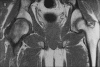

Figure 4

Coronal T1-weighted image shows homogeneously hypointense marrow edema, with normal left hip